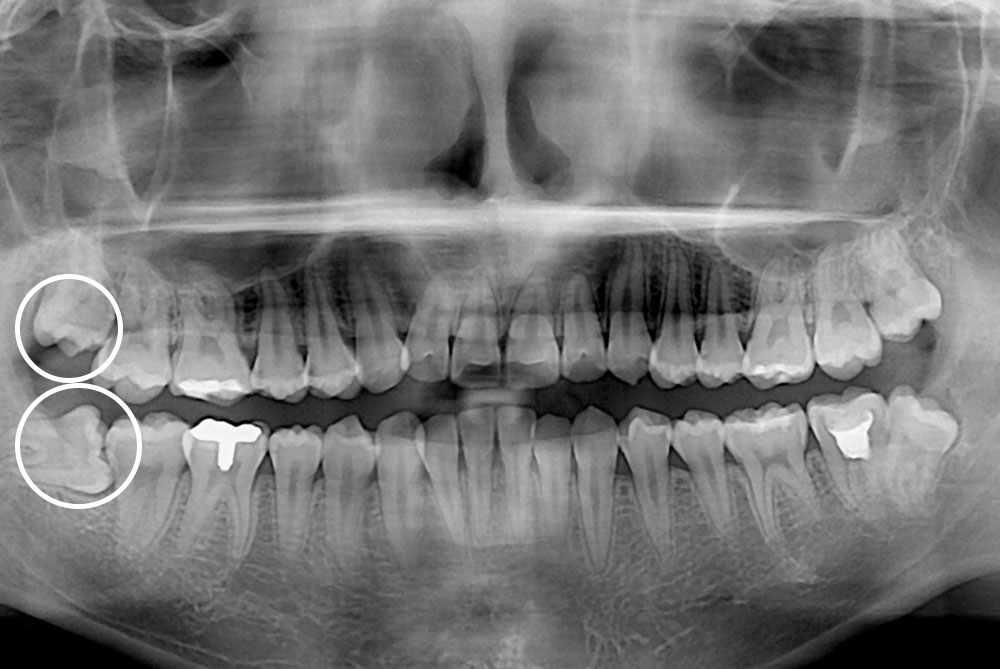

[사랑니] 매복 사랑니 발치

치료후 : 2018-03-23

세종치과는 구강악안면외과학 박사이신 원장님이 발치하는 치과입니다.